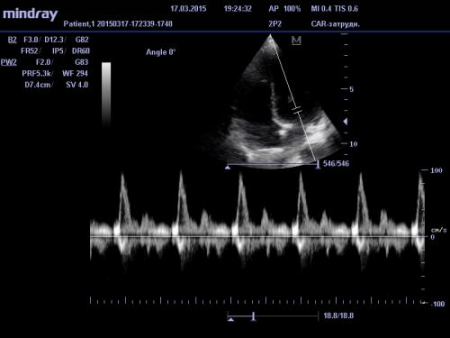

Трехмерное (доплеровское УЗИ).Сегодня используется наиболее часто, так как дает наиболее полную информацию о кровотоке и анатомических пространствах сердца. С помощью современных средств программирования современные аппараты могут показать объемное изображение органа в реальном режиме времени, что значительно облегчает задачу диагностики.